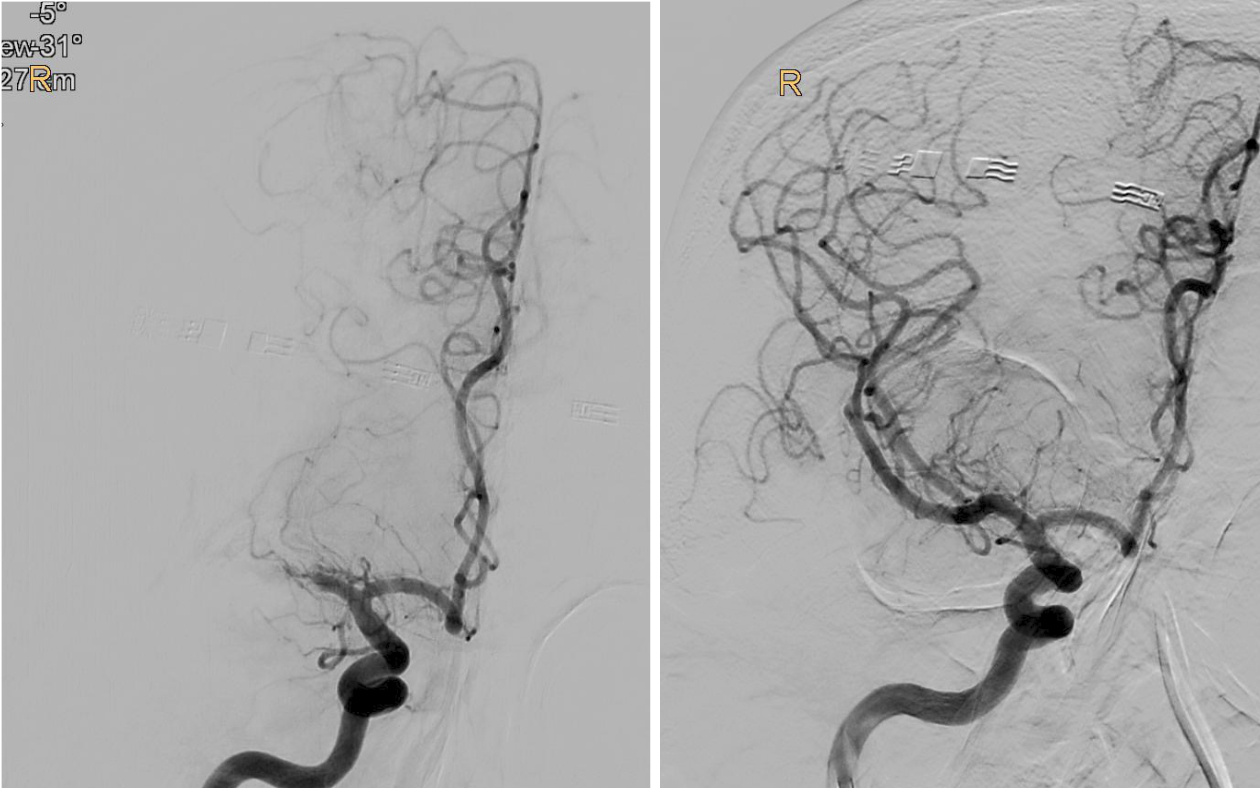

BU: Verschluss des mittleren Hirngefäßes in der Angiographie dargestellt (l.), und wieder eröffnet (r.). Bilder: Univ.-Klinik für Neuroradiologie

„Bei der Thrombektomie bringen wir mit einem Spezialkatheter von der Leiste ausgehend einen Stent an der Stelle des Gehirns ein, wo das Gerinnsel sitzt. Mit einer Saugvorrichtung wird das Blutgerinnsel dann zusammen mit dem Stent herausgezogen. Das Ganze passiert unter Röntgenkontrolle und bedarf viel Erfahrung“, erklärt Gizewski den sensiblen Vorgang. Vor 2015 wurde eine Thrombektomie standardmäßig meist nur durchgeführt, wenn eine Thrombolyse – medikamentöse Auflösung des Gerinnsels – bei den jeweiligen Patient:innen nicht durchgeführt werden konnte. Die großen Studien 2015 konnten zeigen, dass Patient:innen im frühen Stadium sehr von der Thrombektomie profitieren. Im Zuge der TENSION-Studie untersuchten die Expert:innen nun die Effektivität der Thrombektomie bei Schlaganfall-Patient:innen, deren Gehirn schon schwer geschädigt war.

„Bei einem Schlaganfall zählen einerseits Zeit und andererseits die noch verbliebene Sauerstoffversorgung des Gehirns, welche bei den Patient:innen unterschiedlich ausfällt. So genannte Kollaterale, Gefäß-Querverbindungen, können die Durchblutung noch einige Zeit aufrechterhalten. Je weniger solcher Kollateralen vorhanden sind, desto weniger Zeit hat man. Doch auch wenn schon Gewebe untergegangen ist, kann man noch etwas retten, wenn man thrombektomiert. Das konnten wir jetzt mit der TENSION-Studie zeigen“, berichtet Gizewski. Viele der Patient:innen könnten trotz der bedrohlichen Ausgangssituation jetzt wieder ein eigenständiges Leben führen. Nachdem sich der Erfolg der Katheter-Behandlung (insgesamt 125 Patient:innen) in der randomisierten Studie im Vergleich zur besten konservativen medizinischen Behandlung (128 Patient:innen) schnell gezeigt hatte, wurde die Studie frühzeitig beendet.